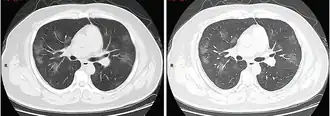

КТ грудной клетки иногда может помочь идентифицировать и охарактеризовать патологию лёгких и дать неспецифические результаты при инфекции COVID-19. Систематический обзор результатов компьютерной томографии грудной клетки у 919 пациентов описал типичное раннее проявление COVID-19 как «двустороннее мультилобарное помутнение матового стекла (GGO) с периферическим или задним распределением».[19] Одно исследование показало, что чувствительность КТ к инфекции COVID-19 составила 98 % по сравнению с чувствительностью ОТ-ПЦР на 71 %; однако это было сделано в китайской провинции Ухань и не подлежит обобщению.[20] Наиболее распространёнными результатами компьютерной томографии были двустороннее затухание матового стекла (пятнистое или рассеянное) с субплевральным доминированием, сумасшедшей укладкой и консолидацией на более поздних стадиях.[21] Эти данные являются неспецифичными и обнаруживаются также при других типах пневмонии. Небольшое исследование показало, что китайские рентгенологи продемонстрировали чувствительность 72-94 % и 24-94 % в дифференцировании COVID-19 от других типов вирусной пневмонии с использованием компьютерной томографии.[22] Ни одно исследование ещё не подтвердило точность и дискриминационную ценность компьютерных томографий, чтобы отличить COVID-19 от других вирусных пневмоний. Поэтому CDC не рекомендует КТ для первоначального скрининга, как подчёркивалось в звонке COCA в четверг, 5 марта. Люди с подозрением на COVID-19 должны проходить ОТ-ПЦР, которая является наиболее специфическим тестом.[23]

Типичные результаты компьютерной томографии